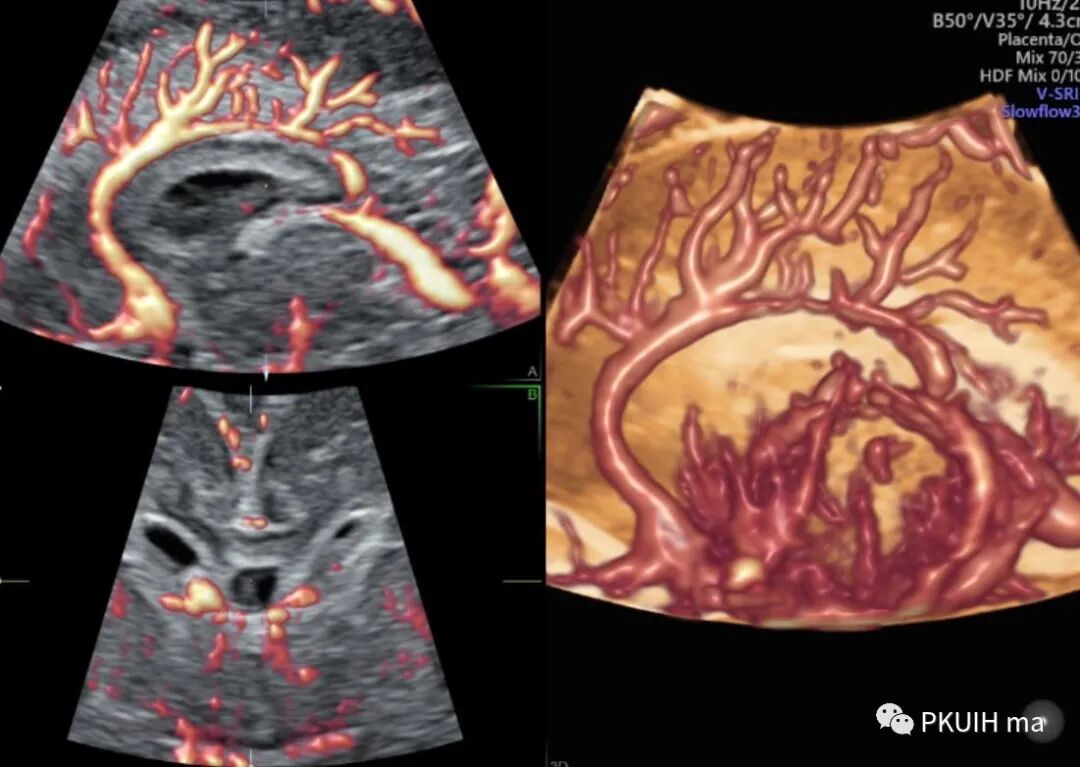

同样用这个功能我们可以很好显示胎儿胼胝体动脉及其分支,效果非常好,对于鉴别胼胝体发育有很大帮助。

另外我们可以采用各种渲染模式来显示胎儿大脑前动脉、胼周动脉及分支